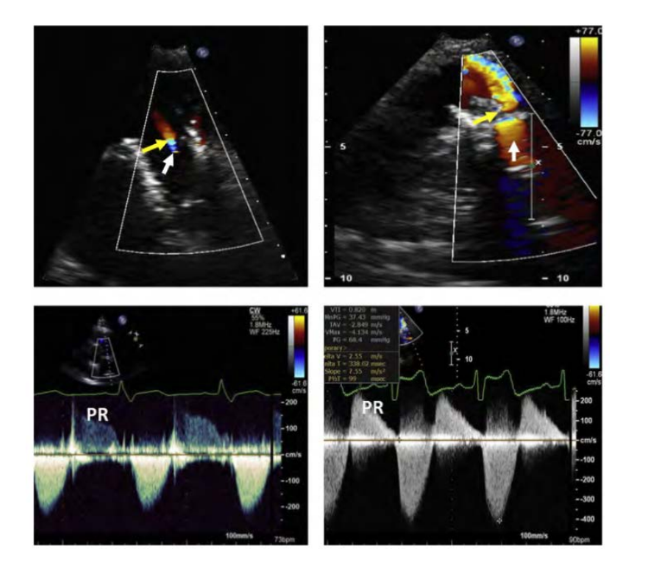

Color Doppler demonstrates what flow into the what?

what assist in determining the severity?

When a valved conduit is present, both stenosis of the conduit and

regurgitation of the valve can occur,

Color, PW, and CW Doppler are used to assist with the evaluation

Color Doppler demonstrates diastolic flow into the RVOT

Jet duration and jet width assist in determining the severity

Severe PR has a what jet duration, as the PA and RV diastolic pressures do what

Severe PR has a short jet duration, as the PA and RV diastolic pressures equalize quickly